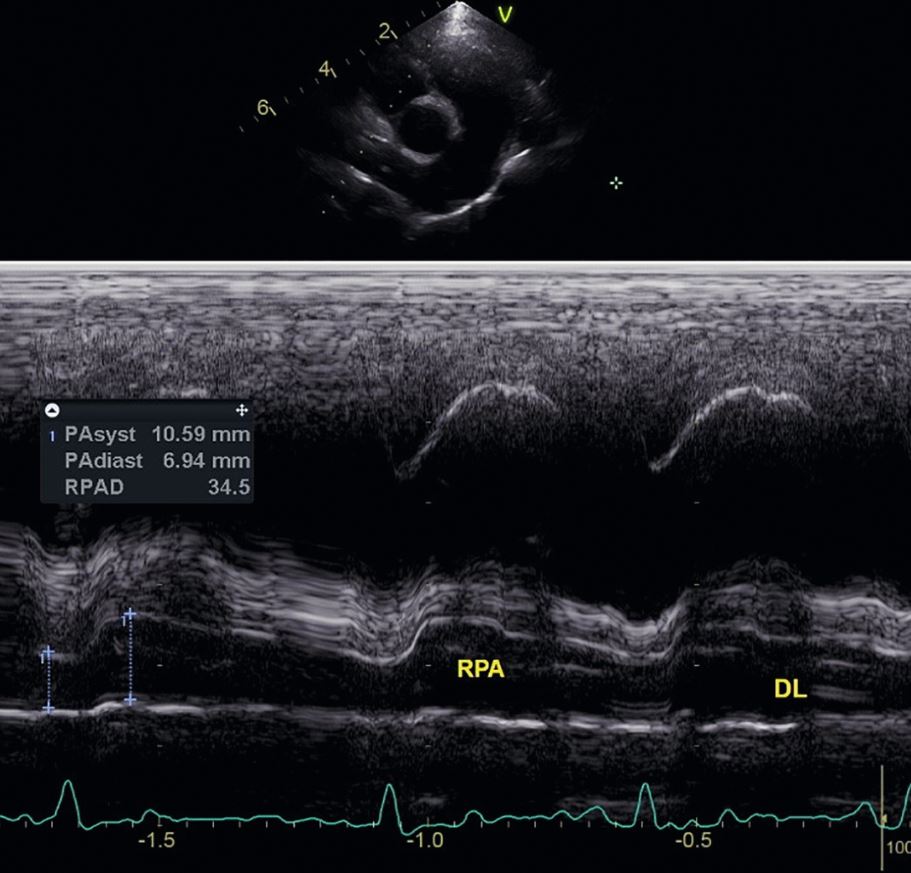

Die Echokardiografie kann weitere Informationen über die Erkrankung und ihre Folgen liefern. Es sollte immer eine komplette echokardiographische Untersuchung erfolgen, um zusätzliche angeborene oder erworbene Herzerkrankungen nicht zu übersehen. Bei den Herzwürmern steht die Beurteilung einer pulmonalen Hypertonie im Vordergrund. Zur Beurteilung des Lungendruckes kann der Dehnbarkeitsindex der rechten Pulmonalarterie herangezogen werden [Abb.2]. Dieser wird insbesondere bei Hunden mit Herzwürmern beschrieben [3], [5] [Tab.1].

| Lungendruck | RPAD |

|---|---|

| normal | >35% |

| leichter PH | 28-35% |

| mittelgradiger PH | 23-27% |

| schwerer PH | >23% |